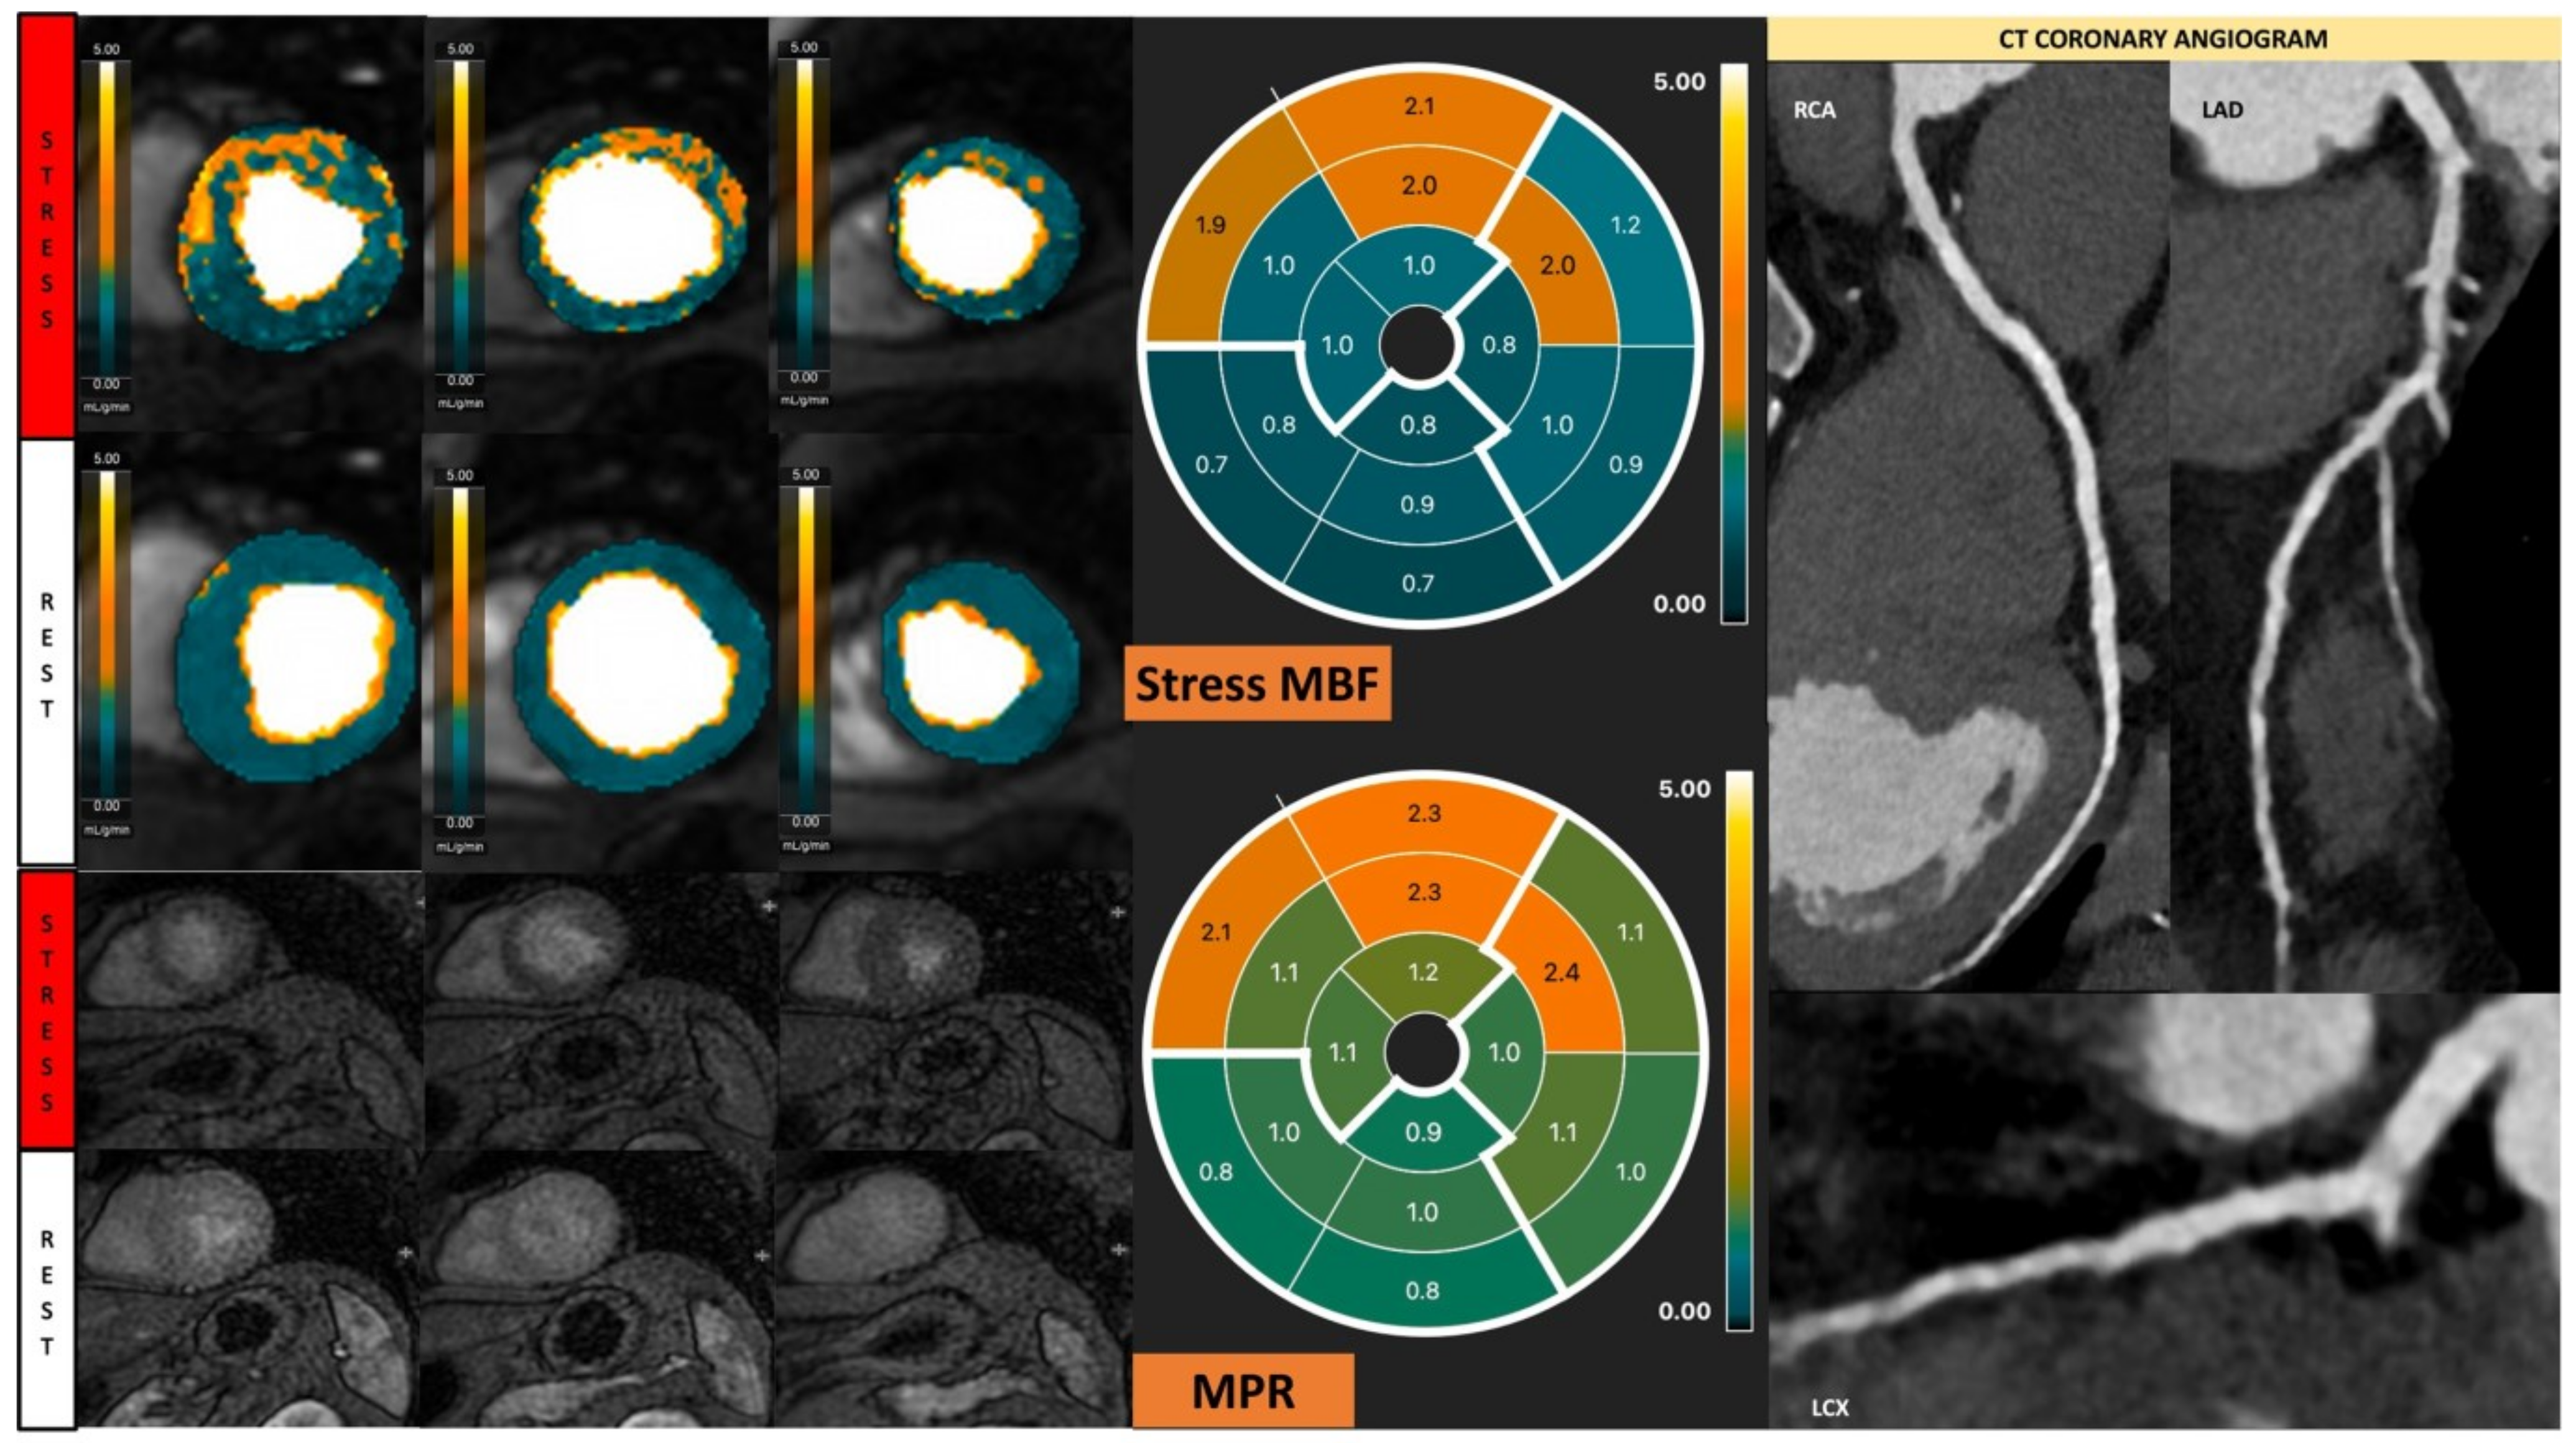

Likewise, in dilated cardiomyopathy (DCM), vasodilator stress-rest perfusion is performed to determine the presence of inducible ischemia [13]. Even if DCM is considered a non-ischemic myocardial disease, the affected patients usually show diffuse myocardial hypoperfusion (Figure 8) [85]. A recent quantitative stress CMR study showed that DCM patients had significantly reduced stress MBF and global MPR with increased rest MBF versus normal controls, likely due to an increased hemodynamic load and structural alteration of the coronary microvasculature [86,87]. Furthermore, coronary vasodilatory dysfunction was correlated with worse LV systolic function [86]. The results from stress CMR revealed the myocardial damage in DCM was caused by an impaired coronary vasodilatory reserve, rather than chronic myocardial hypoperfusion. In the future, CMD detected by stress CMR may serve as the innovative target in DCM patients, and the long-term prognosis needs to be investigated.

Figure 8.

Quantitative stress CMR examination of dilated cardiomyopathy. Female patient in her 60s with dilated cardiomyopathy and phospholamban genetic mutation. Patient underwent stress CMR, having presented with symptoms and signs of heart failure. Top left panel of six images shows quantitative perfusion images with reduced global myocardial blood flow (MBF) during stress. Lower left panel of stress perfusion images shows no stress-induced perfusion defect. Stress MBF and myocardial perfusion reserve bulls-eye plots objectively demonstrate this low perfusion. Coronary computed tomography multiplanar reformat images of the three main coronary arteries show no significant coronary artery disease.